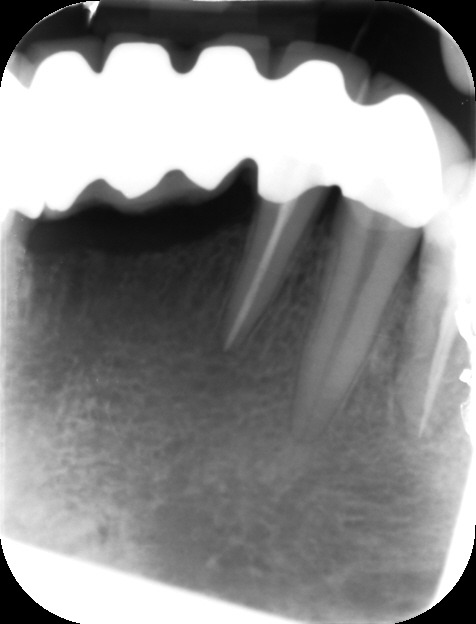

During the consultation, the dentist will first listen to your concerns and carry out appropriate tests to identify the right tooth that is causing pain. As a part of the diagnosis, your dentist will carry out various clinical tests to identify the right tooth and will take some radiographs which can aid in the diagnosis.

An access cavity is placed on the surface where the patient bites, to reach the root canals of the tooth. Once all the canals are identified, small files are used to remove the infected pulp.

Files of different sizes are used to eliminate bacteria and infection and to shape the canals. The canals are disinfected thoroughly with irrigants and later the canals will be sealed in 3 dimensions with a special medicament called gutta-percha to prevent reinfection of the tooth and the access cavity will be sealed with a temporary filling.

After a few weeks, the tooth will be checked and when all the infection has cleared, a crown will be usually required to protect the restore the tooth to function.